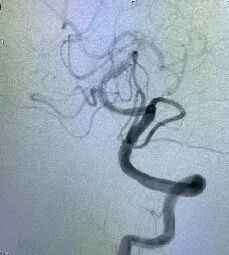

术后影像及检查

此例病人术后第2天言语功能完全恢复,术后第3天,右手功能有所恢复,术后1周右上肢功能完全恢复。

导丝怎么扩【载药时代 球扩天下】NOVA DES®颅内药物洗脱支架在颅内富穿支区域使用体会二例!_https://www.jmylbn.com_新闻资讯_第22张

导丝怎么扩【载药时代 球扩天下】NOVA DES®颅内药物洗脱支架在颅内富穿支区域使用体会二例!_https://www.jmylbn.com_新闻资讯_第23张

影像结论:左侧大脑中动脉完全开通,达3级再通。